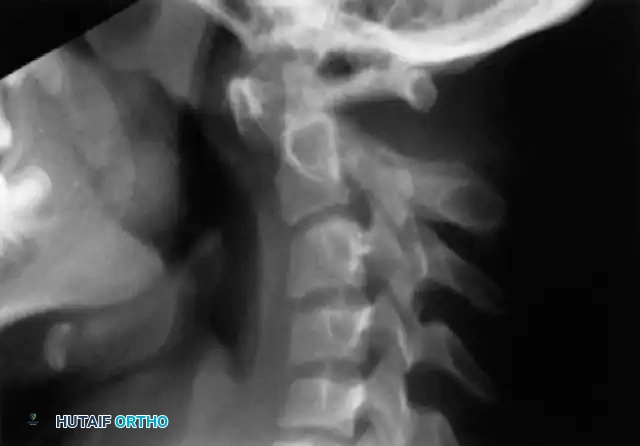

Standard plain radiographs of the craniocervical junction are notoriously difficult to interpret in patients with occipitalization due to overlapping osseous structures and the variable degree of assimilation.

Most commonly, the anterior arch of the atlas is assimilated into the occiput and displaced posteriorly. Approximately 50% of patients exhibit a relative basilar impression caused by the loss of height of the assimilated atlas. The posterior fusion often consists of a small bony fringe or a fibrous band directed caudally into the spinal canal, which may not be visible on plain films but is a primary driver of posterior neurological compression.

Flexion and extension lateral cervical spine radiographs are a critical component of the initial evaluation to assess for atlantoaxial instability.